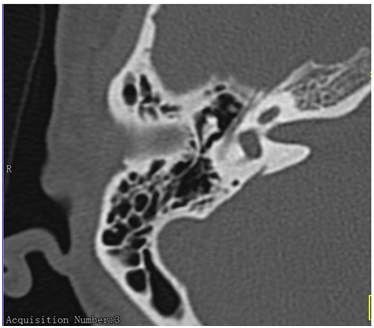

There was no negative effect of medication on the patient during the treatment. After two months of treatment, the normal hearing was restored and type A of tympanogram was obtained. The results of CT scan image of the ear are presented on Figure 3 & 4.

Figure 3 MEM, 50 yrs female, OMC with polyps, R ear after treatment.

Figure 4 M EM, 50 yrs, female, OMC with polyps.

As immunosuppressive drug the option was a low-dose prednisolone with its glucocorticoid effect.9,10 As it is visible in the Figure 3 & 4, a resolution of the disease is obtained with no need for surgery. The patient had no recurrence of the ear disease.